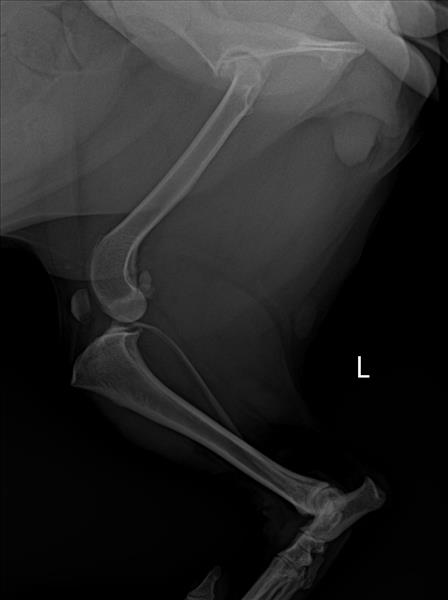

우선 11kg의 비숑입니다.

혼자 신나서 빠르게 움직이며 가벼운 점프를 하다

심한 고통을 느꼈는지, 비명을 내지르기 시작했습니다.

의사선생님께서 말씀하신건 파열은 되지 않았지만

밀린 상태지만 파열이 될 가능성도 있으니

철두철미한 관리가 필요하다, 였습니다.

엑스레이 사진을 봐주시고 선생님의 조언을 간절히 기다립니다. 계속 관리해주고 체중관리와 더불어 보조기 착용을 한다고해서 정상 보행이 가능해질수 있을까요?